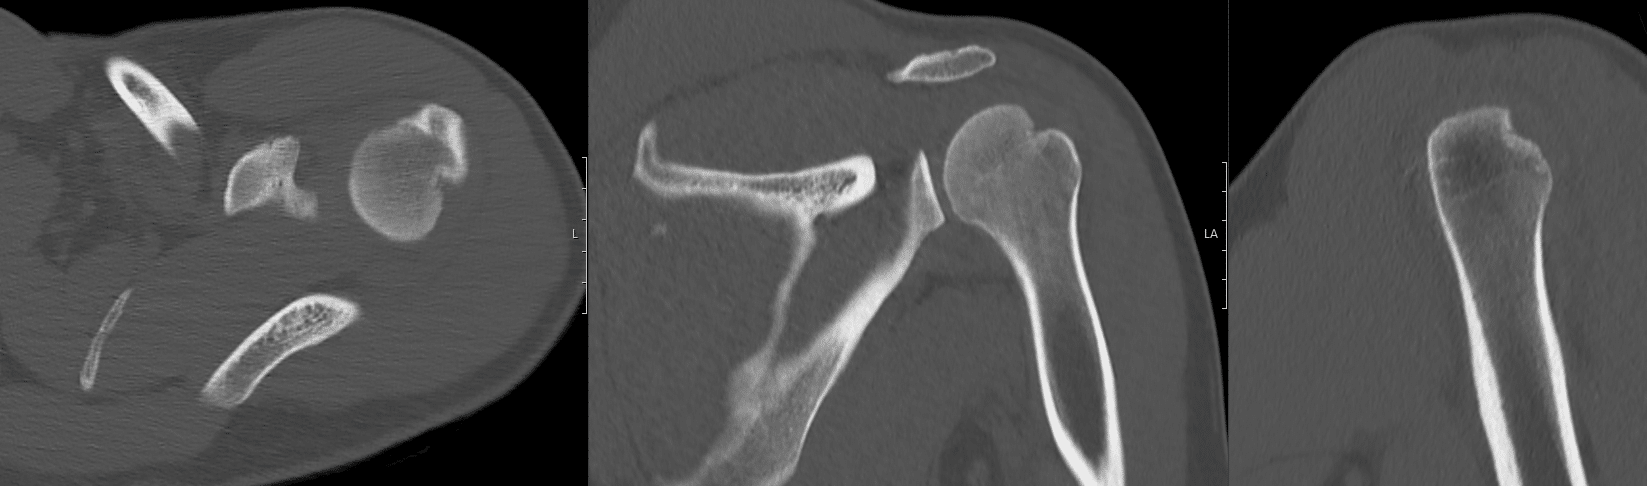

1. Hill-Sachs deformity in the posterior aspect of the humerus.

2. Comminuted displaced osseous (bony) Bankart lesion involving the anterio-inferior glenoid fossa (6-10 o’clock).

3. Comminuted laterally displaced fracture of the coracoid process.

4. Associated joint effusion and surrounding soft tissue haematoma.

Shoulder dislocations may be complicated by Hill-Sachs or Bankart lesions. These often occur during shoulder dislocations when the humeral head is forcibly impacted on the glenoid rim. These injuries can contribute to future shoulder instability, and their management is determined by the size of the injury and associated instability of the shoulder joint.

Hill-Sachs defects are cortical depressions of the posterolateral aspect of the humeral head. They occur in up to 40% of anterior shoulder joint dislocations (1) and are best seen on AP X-rays with the arm held in internal rotation. These injuries may be managed nonoperatively if the bony defect is small (<20% of the articular surface of the humeral head) and the glenohumeral joint remains stable during desired activities (3). Surgical management involves bone grafting or placement of soft tissue within the defect.(3).

Bankart lesions are injuries at the anteroinferor aspect of the glenoid labrum complex. They are classified as bony Bankart lesions (bone fragment avulsed) and soft tissue Bankart lesions (no bone avulsed). Management of bony Bankart lesions is similar to that of Hill-Sachs deformities in that these injuries are managed nonoperatively if the bony defect is <20% of the surface area of the inferior glenoid (5). Soft Bankart lesions occurring in young patients with first-time dislocation are often managed with arthroscopic repair. Surgical management involves suturing the labral fragment back to the glenoid rim using suture anchors. Early discussion with Orthopaedic specialists is recommended to guide management.

This patient was placed in a broad arm sling and referred to orthopaedics outpatient rooms for review in 2 weeks from time of injury.